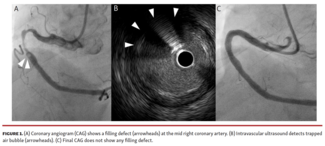

Rintaro Mukai, MD; Takashi Kajiya, MD, FESC, FACC; Nobuhiko Atsuchi, MD, PhD; Mitsuru Ohishi, MD, PhD

A correct diagnosis of “filling defect” is necessary because device selection is different for each case. IVUS is useful for differential diagnosis of calcification, thrombus, or air bubble.